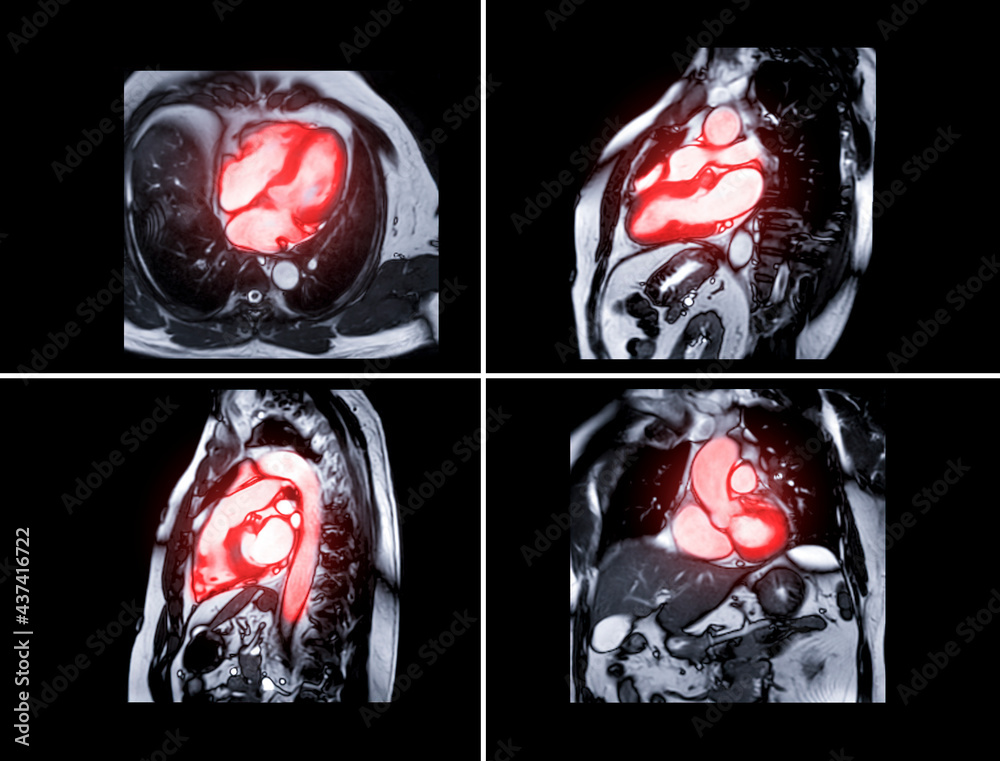

From stock.adobe.com

Collection of MRI heart or Cardiac MRI resonance imaging of What Is A Heart Mri What is a cardiac mri? A cardiac mri is a noninvasive test that uses a magnetic field and radiofrequency waves to create detailed pictures of your heart and arteries. What is mri of the heart? Cardiac mri scanning is a noninvasive imaging test that can be very helpful in defining the anatomy and function of the heart and major blood. What Is A Heart Mri.